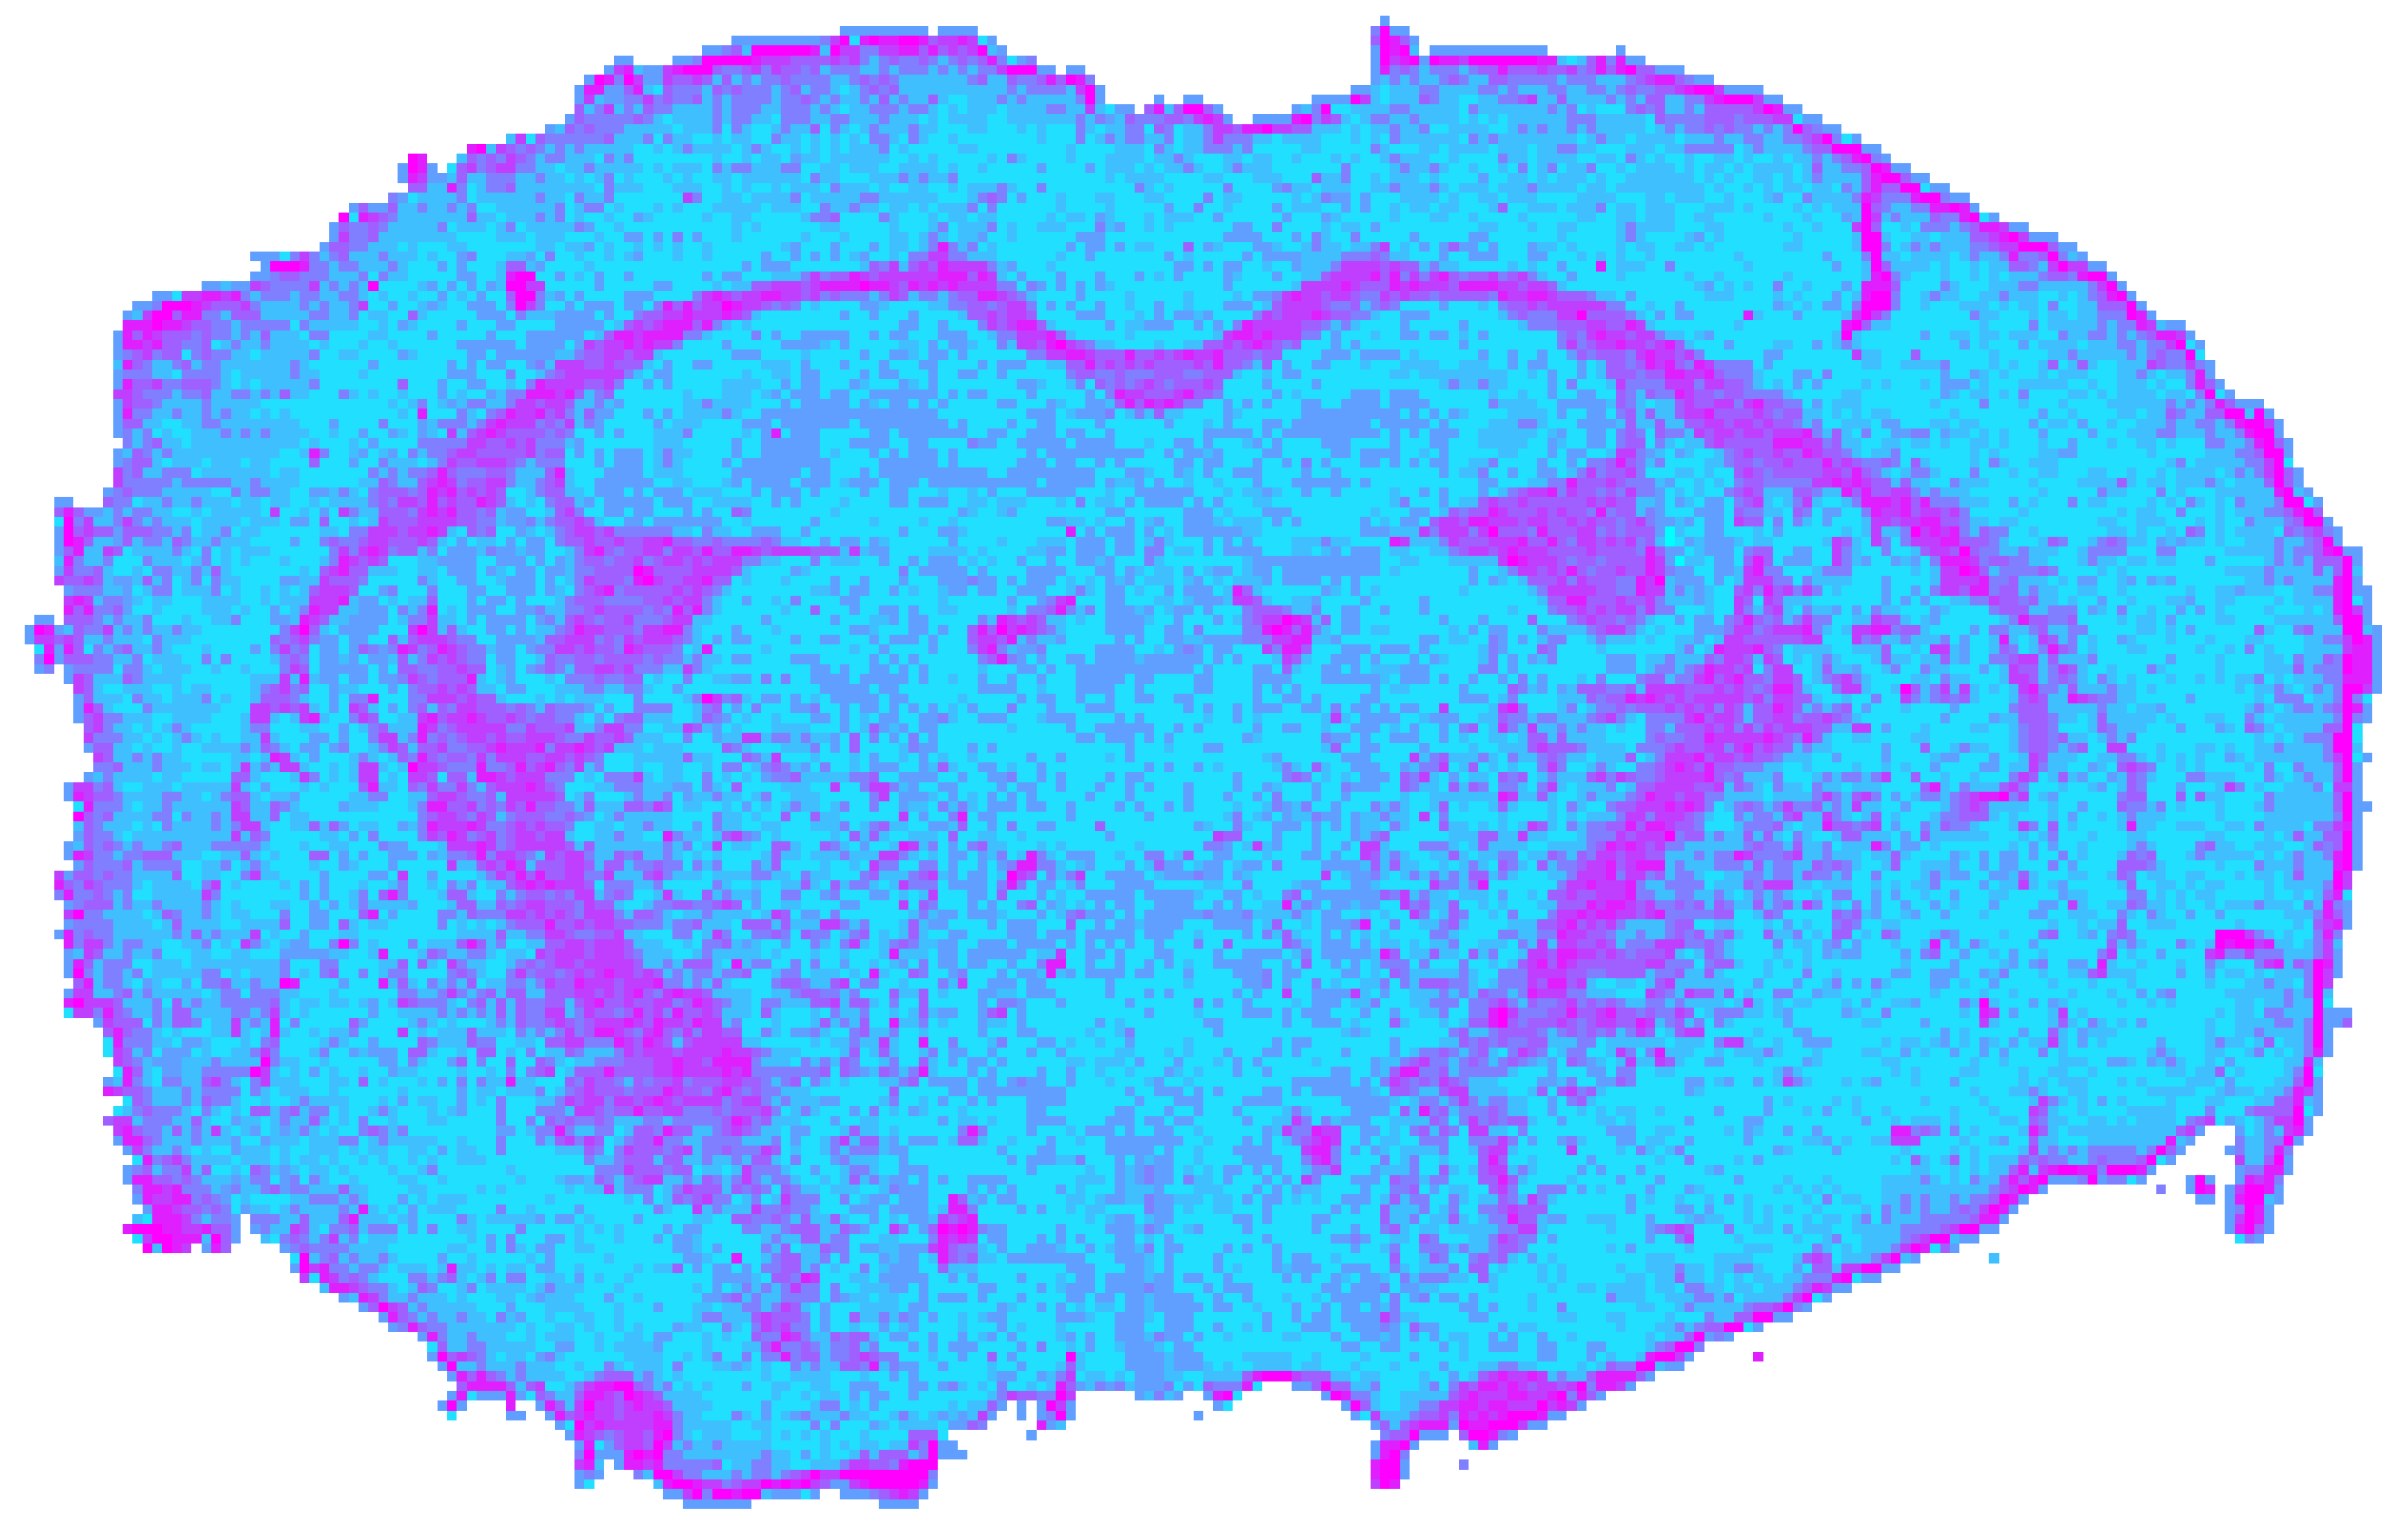

3.1. NIR Processing Results

After undergoing modality-specific preprocessing, which included spectral reference correction, spike removal, background removal, min–max normalization, and SPA-based band reduction to k = 20, the NIR datacube produced a stable clustering solution with a mean silhouette coefficient of sNIR = 0.5879. This value indicates a coherent but moderately overlapping cluster arrangement.

Figure 5 shows that white-matter structures exhibited the strongest detectability. The corpus callosum, stria medullaris thalami, columnae fornicis, and fimbria hippocampi were all consistently identified as compact clusters. This reflects NIR reflectance sensitivity to myelinated tissue. Gray matter structures exhibited weaker contrast. The thalamus and hypothalamus were only partially separable, and the hippocampus remained undetected. CSF compartments were also not resolved. As shown in Table 3, the NIR clusters corresponding to white matter exhibit reduced water absorption and pronounced lipid-related CH overtone and combination bands. In contrast, clusters associated with gray matter and CSF are characterized by comparatively stronger water/protein absorption and weaker lipid contributions. Consequently, lipid-dominated clusters predominantly map to myelinated fiber tracts, while water- and protein-dominated clusters predominantly map to gray matter and fluid-filled compartments.

Figure 5. Spatial clustering map of the preprocessed NIR datacube obtained with Mini-Batch KMeans (k = 9), showing the unsupervised segmentation of the mouse brain section into spectral tissue classes.